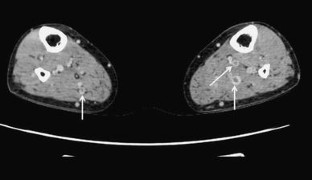

Fig. 1